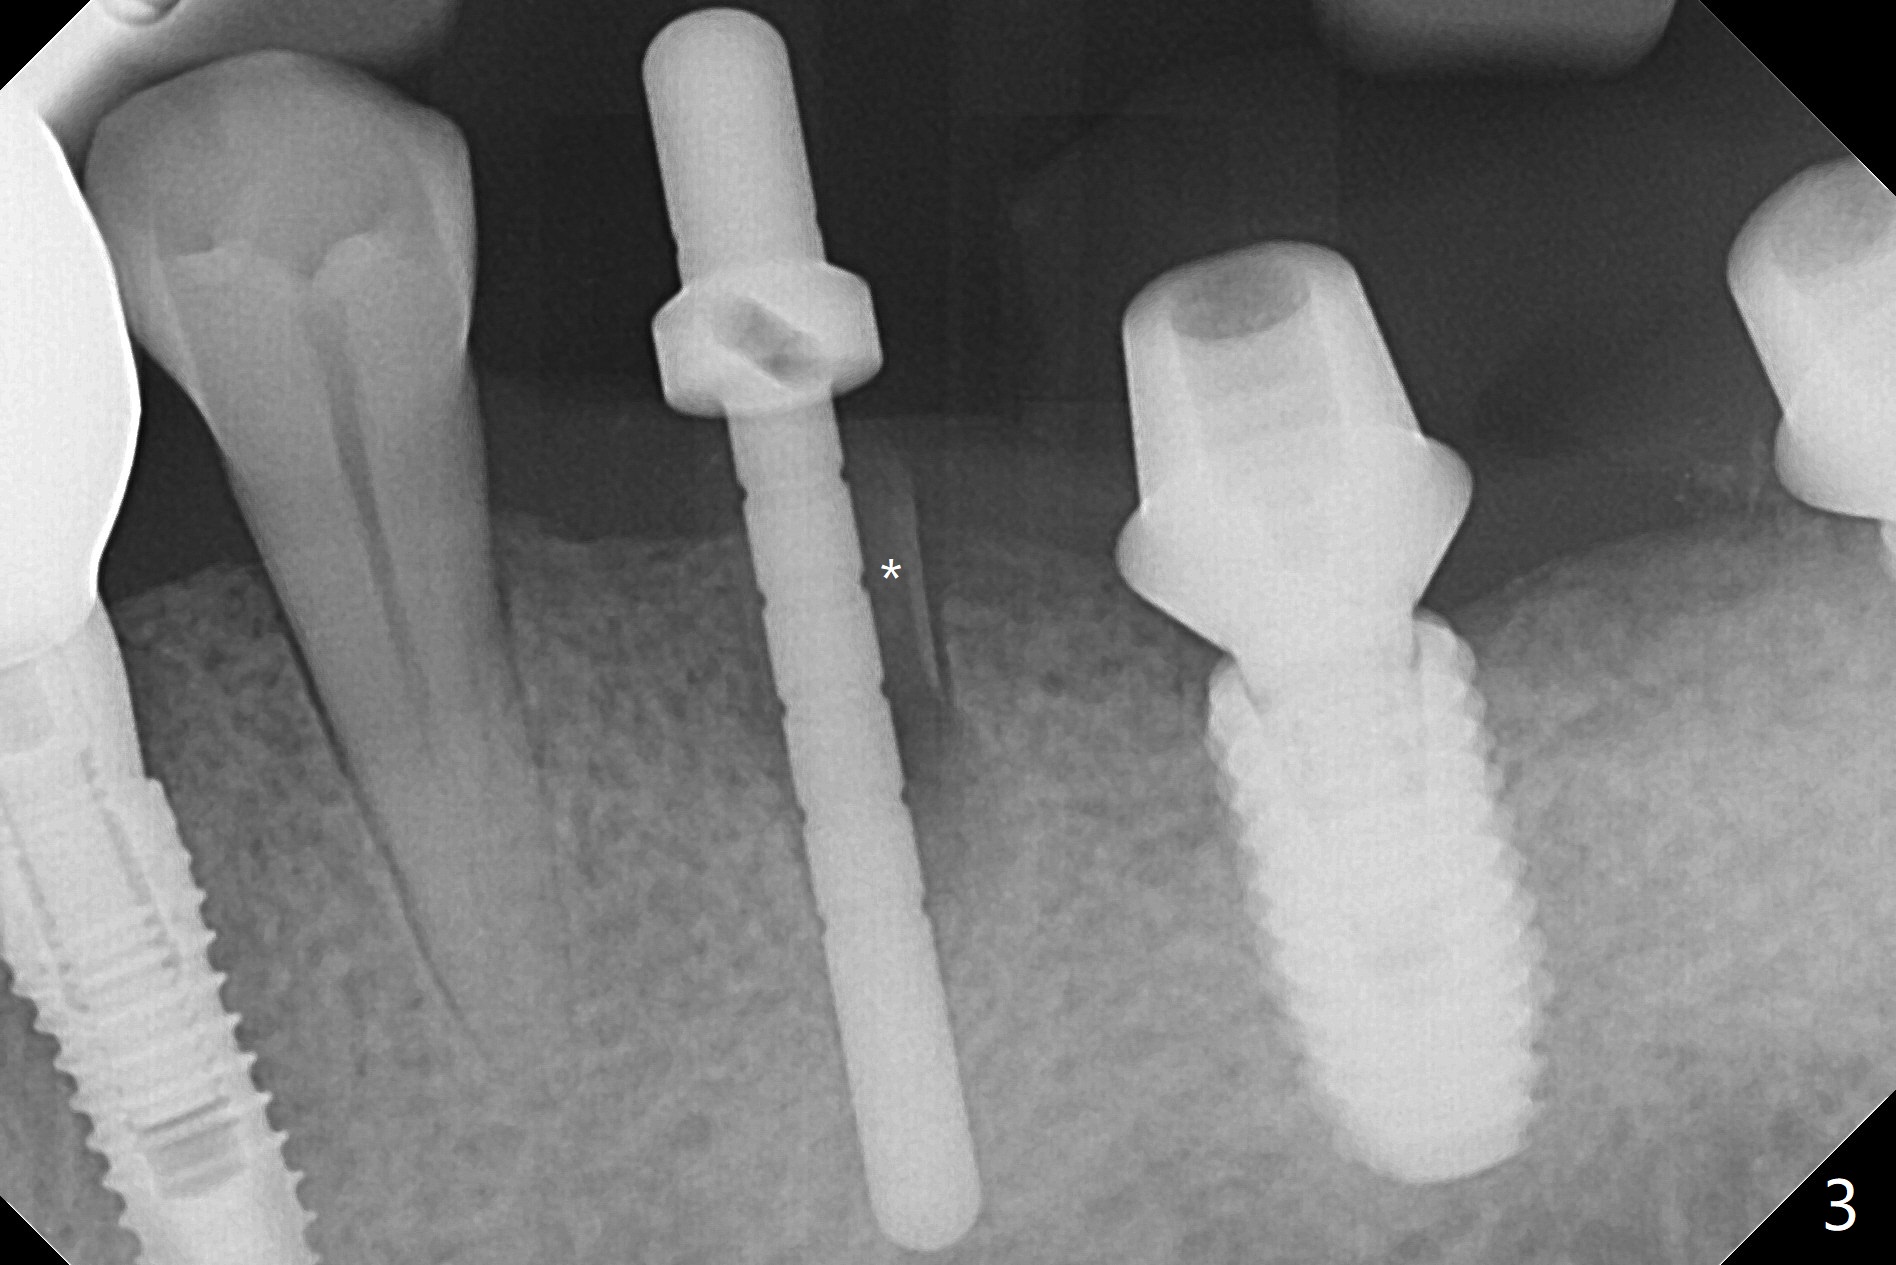

Socket Shield is conducted at #20 (Fig.1-3 *). With placement of a 4x11.5 mm implant equicrestal lingually, a 4.5x6(2) mm temporary abutment is unable to be seated incompletely (Fig.4 black <) because of proximal crestal interference (white arrowheads). After use of a 5.5 mm profile drill, a 5.5x5 mm healing abutment is apparently seated completely (Fig.5). Upon close look, the abutment at #19 is also incompletely seated. In fact #18/19 temporary crowns and #19 abutment are loose. A 6.8x4 mm healing abutment is later placed at #19. Periodontal dressing is applied at #18-20. In fact buccolingual control of osteotomy is not easy with free hand. A smaller implant (e.g., 3.5 mm) may be easier.